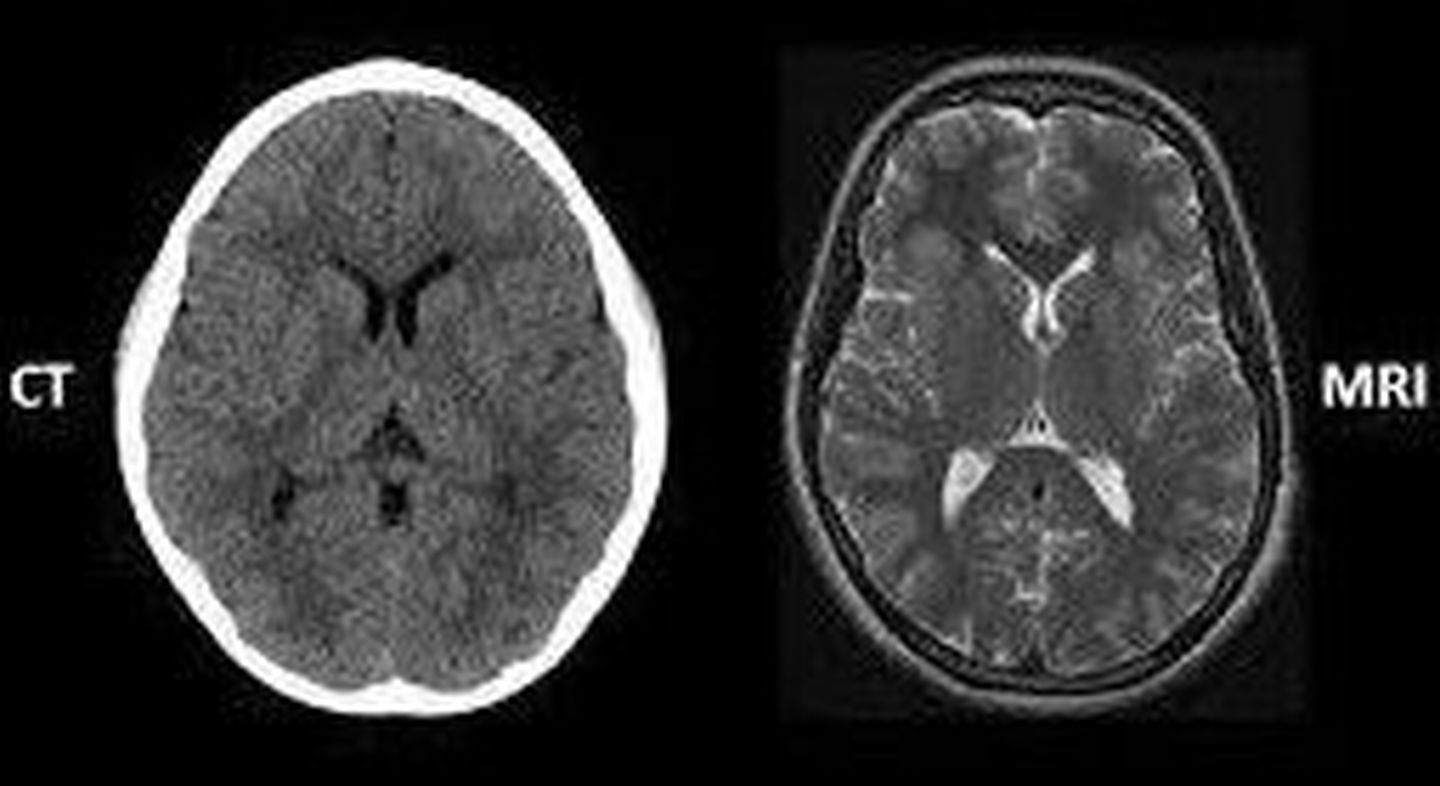

How to differentiate between ct and MRI of brain 1- in MRI Imaging you can see details of bain tissue but in CT Scan you cant and in CT you just see some Gray and White thigns 2- in CT Scan The Bony Skull is prominent White But in MRI it is not like this 3- in CT Scan Brain Tissue Appears as Tight Attached to The White Bone But in MRI Image, There is a Black Space Around Brain